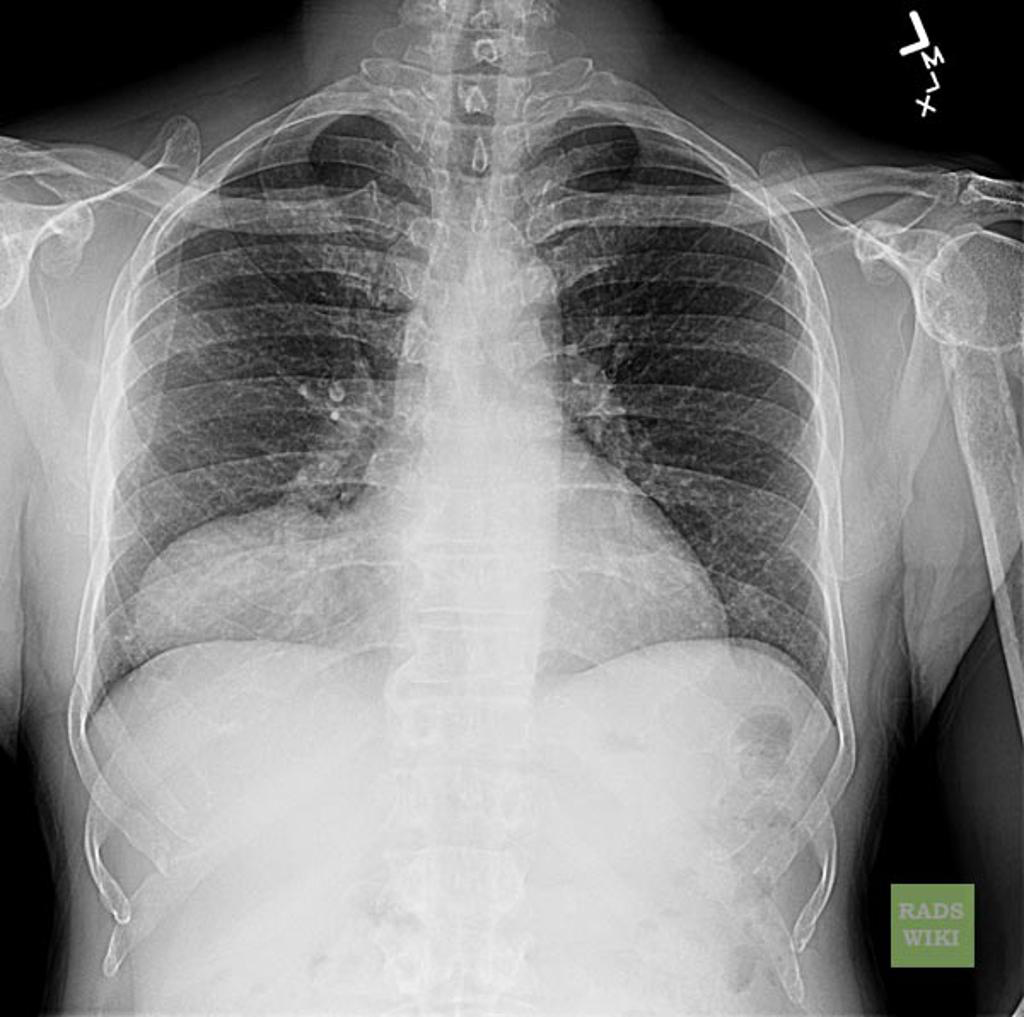

Re Pulmonary alveolar proteinosis-PAP

b) Crazy paving with septal thickening and GGO

c) Bronchoalveolar lavage

What are the DDx for crazy paving? (5) ie septal thickening and GG